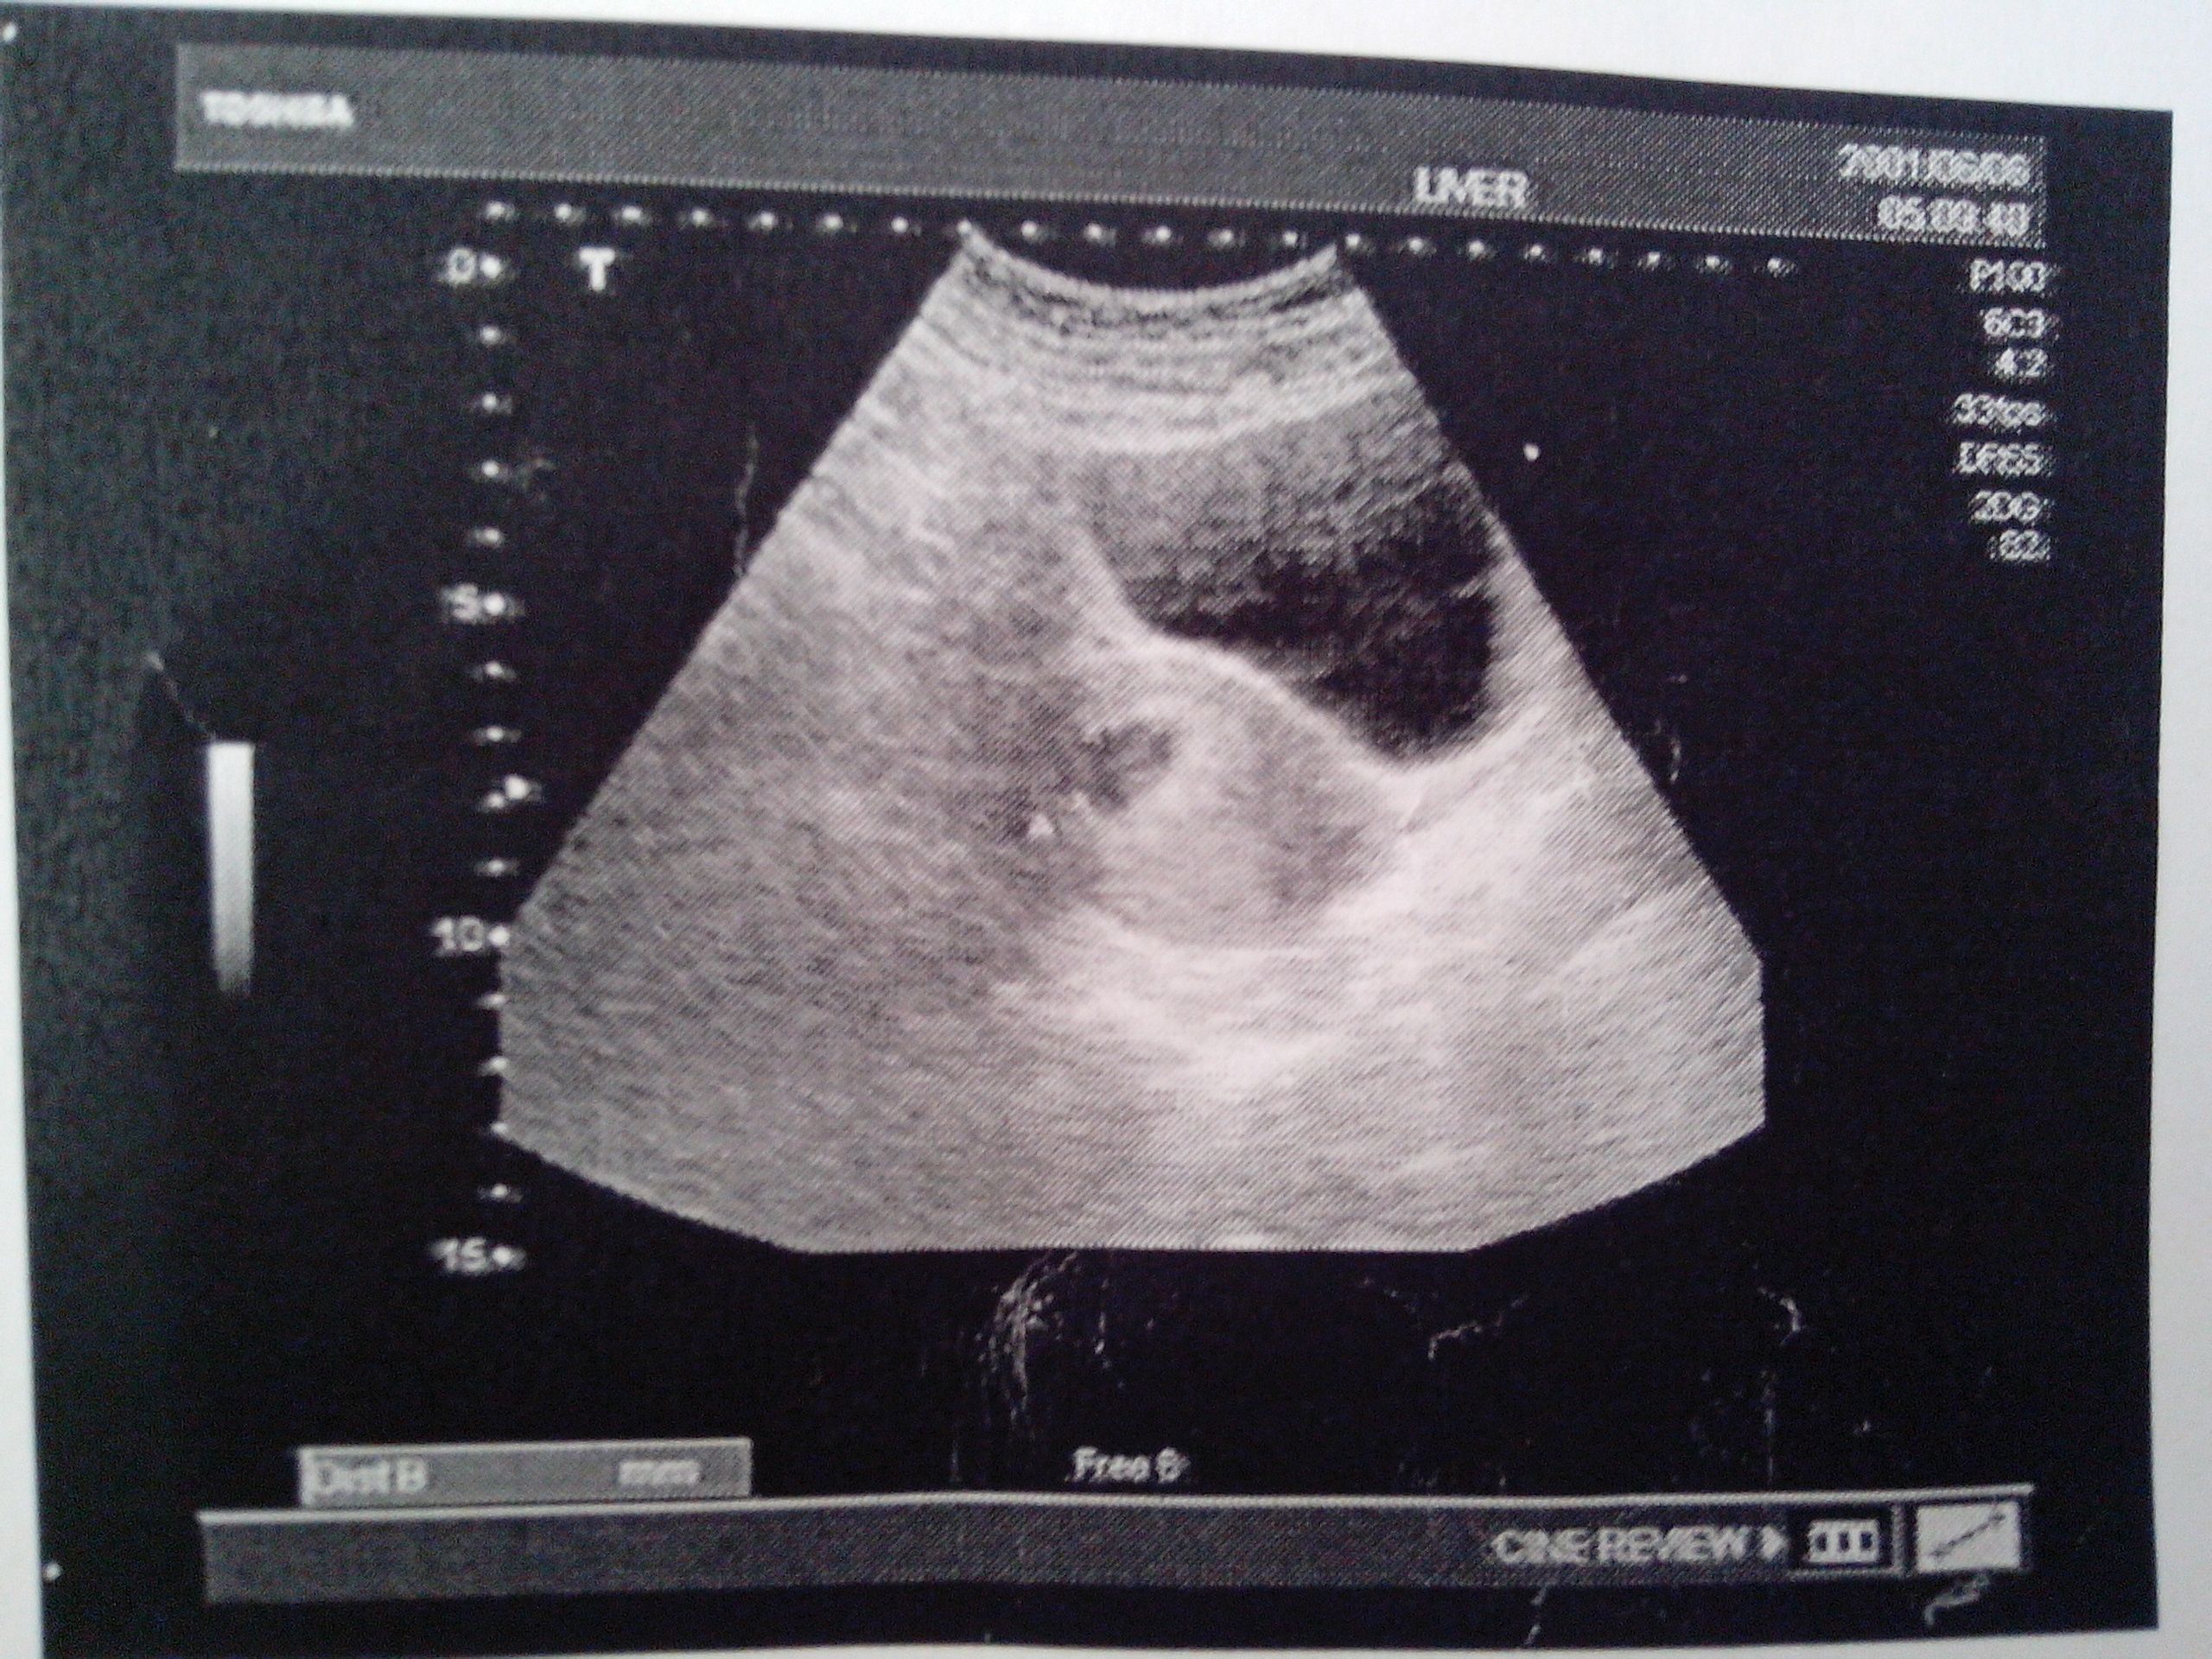

这是我怀孕6周6天的黑白b超图,有孕囊吗?求帮助

孕6周6天 孕囊情况及卵巢大小